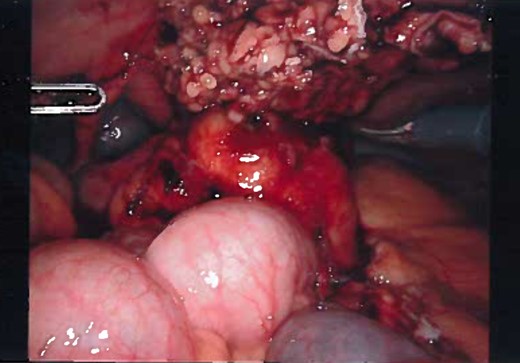

Patient was administered general anesthesia with placement of endotracheal tube. She was placed in lithotomy position (stirrups), both arms tucked at sides, strap secure across chest and a bair hugger (warmer) was placed around upper chest/head/neck area. Our patient was prepped with betadine for a vaginal/perineal prep and chloroprep was used on the abdomen. After sterile draping of the patient, and official time-out with all in agreeance, the Urologist evaluated the bladder with a cystoscopy using a 70° scope to survey for any persistent urachal abnormalities, and confirmed that no fistula/congenital abnormalities from inside bladder. General Surgeon scrubbed in and proceeded with insertion of veress needle and insufflated the abdominal cavity with CO2. Once the abdominal pressure reached 15 mmHg, General Surgeon used a 5 mm/0° laparoscope inside a 5 mm first-entry trocar and watched himself insert the trocar through each layer until passing through the peritoneum and into the abdominal cavity. Two 8 mm robotic Xi trocars were inserted, a 12 mm AirSeal Assistant port, and the 5 mm first entry port was replaced with a third robotic 8 mm cannula. Altogether 3–8 mm robotic ports, a 12 mm assistant port, and a 30° robotic scope was utilized during the case. Docking of the robot followed port placement with ‘renal right’ selected on the patient cart while the patient was placed in slight Trendelenburg. Da Vinci Xi instruments used were a fenestrated bipolar and a monopolar scissor to begin dissection. Initial survey of abdomen confirmed that there is an extension of a structure from the dome of the bladder to the posterior surface of the umbilicus (Fig. 4) and more suggestive of an infected urachal cyst. Further evaluations revealed that the cyst surrounding the umbilicus is inflamed and had multiple pus filled cavities. A complete resection of the cyst and the connecting structure was resected by Da Vinci Xi robotic system (Fig. 5). The bladder was filled with 300 ml of sterile normal saline mixed with methylene blue dye through the Foley catheter to determine any bladder otomies from the dissection. None were present. Urologist over sewed a thin area of the bladder with a 3-0 vicryl SH suture (Fig. 6). Complete resection of the cyst was performed successfully (Fig. 8). Slight irrigation was used to check for bleeding and the specimen was put in an endocatch bag to be retrieved when ports are ready for removal. A 19 Fr Blake drain was placed in the abdominal cavity and secured with a 2-0 nylon suture. Foley catheter is also indwelling.

Inflamed and necrotic appearance of the urachal cyst with multiple pus filled cavities.

Gross appearance of the urachal cyst resembled an inflammatory and necrotic appearance with multiple cystic cavities (Figs 3 and 7). On pathology, tentative diagnosis of the specimen was confirmed as an urachal cyst. The appearance of an ulcerated cyst wall noted with marked fibrosis, acute and chronic inflammation with focal abscess, foreign body giant cells, and fibrous adhesions, consistent with history of infected urachal cyst and no evidence of malignancy. Intra-operative culture of urachal cyst provided contents positive for Escherichia coli, and negative for fungal material. The patient had an uneventful post-operative course. We followed up the patient in 2 weeks and again in 3 months in the outpatient clinic. During the follow-up, patient reported that removal of the cyst helped her abdominal pain, urinary tract symptoms have completely resolved and constipation was improve pertinently.